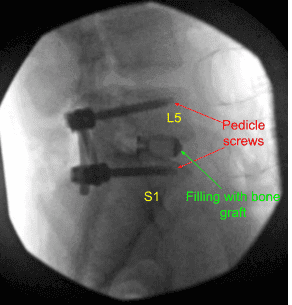

Una vez realizada la disección, se decidió colocar tornillos pediculares en ambos pedículos de S1 y L5. Se utilizaba un taladro para marcar un agujero piloto y una palanca de cambios para guiar el agujero a través del pedículo de S1 a ambos lados bajo guía fluoroscópica. Se utilizaba el sonido de la punta de la bola para comprobar la integridad del canal.

Luego se insertaron 40 mm x 6 mm de tornillos pediculares (Depuy Synthes) en cualquiera de los pedículos de S1 y se revisaron mediante fluoroscopia y se comprobaron que estaban en posición satisfactoria. De manera similar, se realizó un agujero piloto utilizando un taladro a ambos lados del pedículo de L5 seguido de una palanca de cambios para encontrar el camino bajo fluoroscopia. Se volvió a usar una sonda con punta de bola y se encontró que todas las paredes estaban intactas. De nuevo, se hacía el golpeteo y se insertaban tornillos pediculares de 6 mm x 45 mm en cualquiera de los pedículos.

Se insertó una jaula de prueba y se revisó con fluoroscopia y se decidió instalar una jaula de titanio de 9 mm x 36 mm. Se utilizó aloinjerto y se mezcló con injerto autoóseo morselizado de la lámina y proceso espinoso. El espacio entre la jaula y el disco se llenaron con injerto óseo y se insertó y revisó mediante fluoroscopia, encontrando una posición satisfactoria.

Se realizó una irrigación exhaustiva de la herida, se realizó la decorticación del proceso transversal tanto de la L5, el ala sacro como de las partes del lado derecho, y se insertó un injerto óseo sobre el Fibergraft. Las varillas de 45 mm se usaban para conectar ambos tornillos pediculares a cada lado y los tornillos de fijación se insertaban, apretaban y apretaban con apriete.